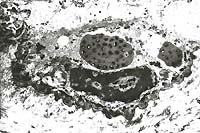

2x

obj

40x

- Case 24-3. Haired skin. The dermis and subcutis beneath

a thickened epidermis is expanded by edema and infiltrating inflammatory

cells which surround and separate normal dermal elements. High

power of the epidermis illustrates multiple brightly eosinophilic

intracytoplasmic inclusions within keratinocytes, multifocal

neutrophilci infiltrates, and parakeratotic hyperkeratosis.

- Case 24-3. Several intracytoplasmic inclusions within

a degenerating cell contain multiple electron dense dumbell shaped

virions characteristic of poxvirus.